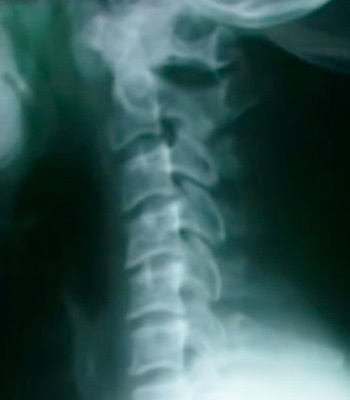

正常な頚椎のカーブ

ストレートネックは長期の首に負担をかける姿勢が続くことでじわじわと首のカーブが無くなりそして、首だけでなく背中や腰、骨盤・股関節に膝などの関節の位置がおかしくなり身体のあちこちで症状を引き起すきっかけになることも多くあります。